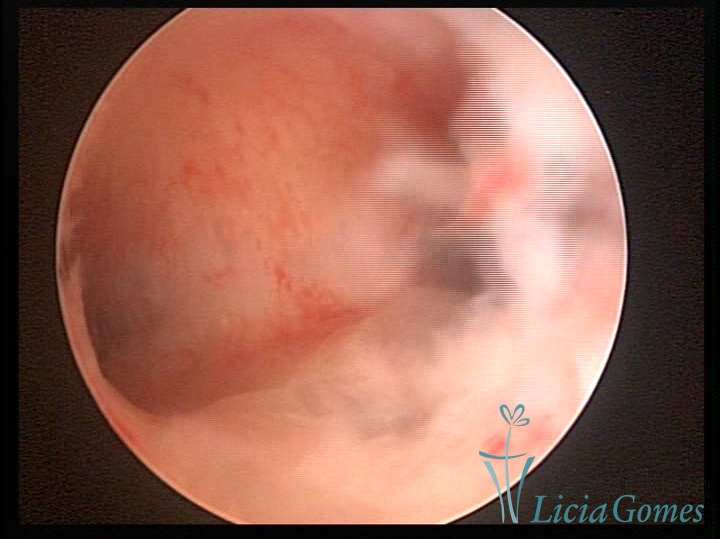

Septate uterus

It probably occurs by the lack of resorption on the middle line, in the merge of Müllerian ducts. The uterus is divided by a partial or total septum which is viewed as a crossbar, not covered by endometrium, which not bleeds when sectioned.

Complete septum when it occupies the whole extension of the cavity, dividing it into two hemicavities.

When this septum occupies only a part of the extension of the uterine cavity, it is considered as incomplete.